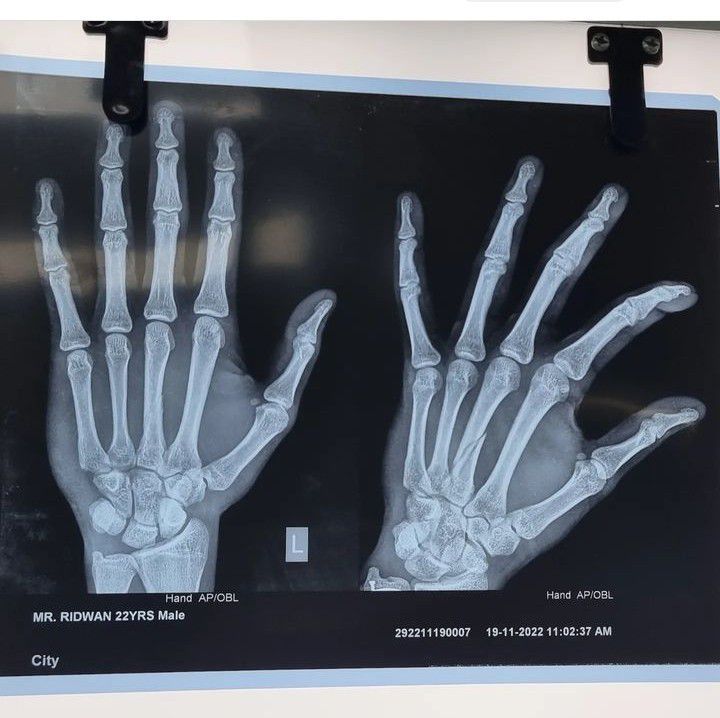

Locate the Fracture

Locate the fracture in this radiograph.